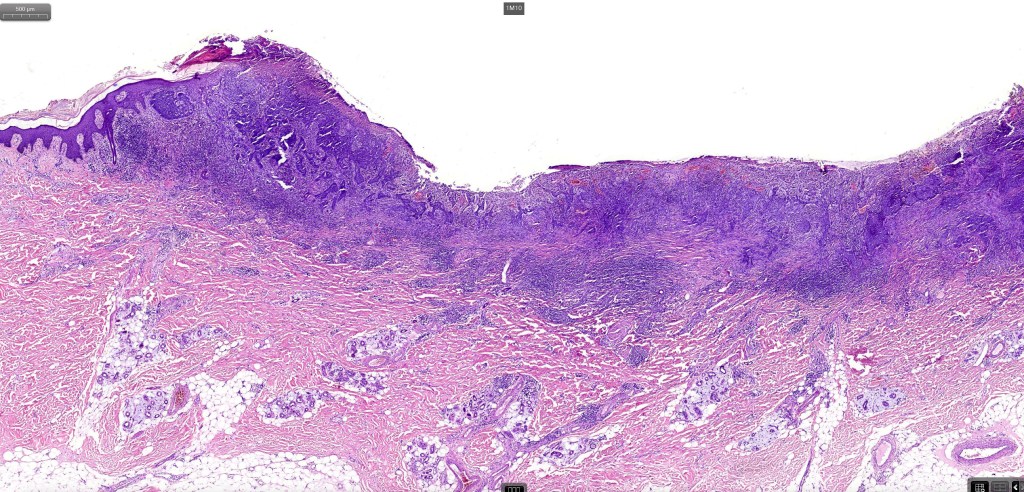

•The tumor commonly arises from the epidermis

•The epithelial component is composed of uniform small, basophilic devoid of desmosomes

•Peripheral palisading

•Retraction artifact with stromal mucin

•A wide variety of histological variants are possible including nodular, nodulocystic, ulcerative, superficial, micronodular, infiltrating/infiltrative, keratotic, basosquamous, pigmented, morpheaform, keloidal, clear-cell, signet-ring cell & granular cell variants, BCC with monster cells, BCC with metaplastic features, BCC with matricial differentiation, basomelanocytic tumor (see separate blog), BCC with thickened basement membrane, BCC with carcinoid-like nuclear palisading & these are illustrated below